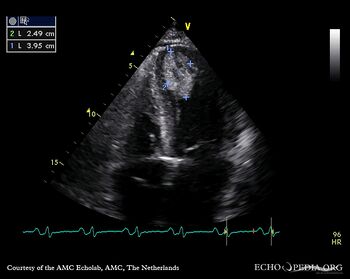

Case 142